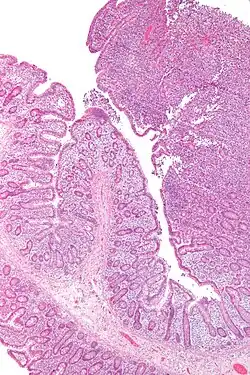

| Micrografia de um linfoma de células T associado a enteropatia (canto superior direito) | |

Linfoma de células T associado a enteropatia (EATL) é um tipo de linfoma das células T que afeta o intestino delgado. É o tipo mais comum de linfoma das células T gastrointestinais, partindo dos linfócitos T entre as células que revestem o intestino delgado.[1]